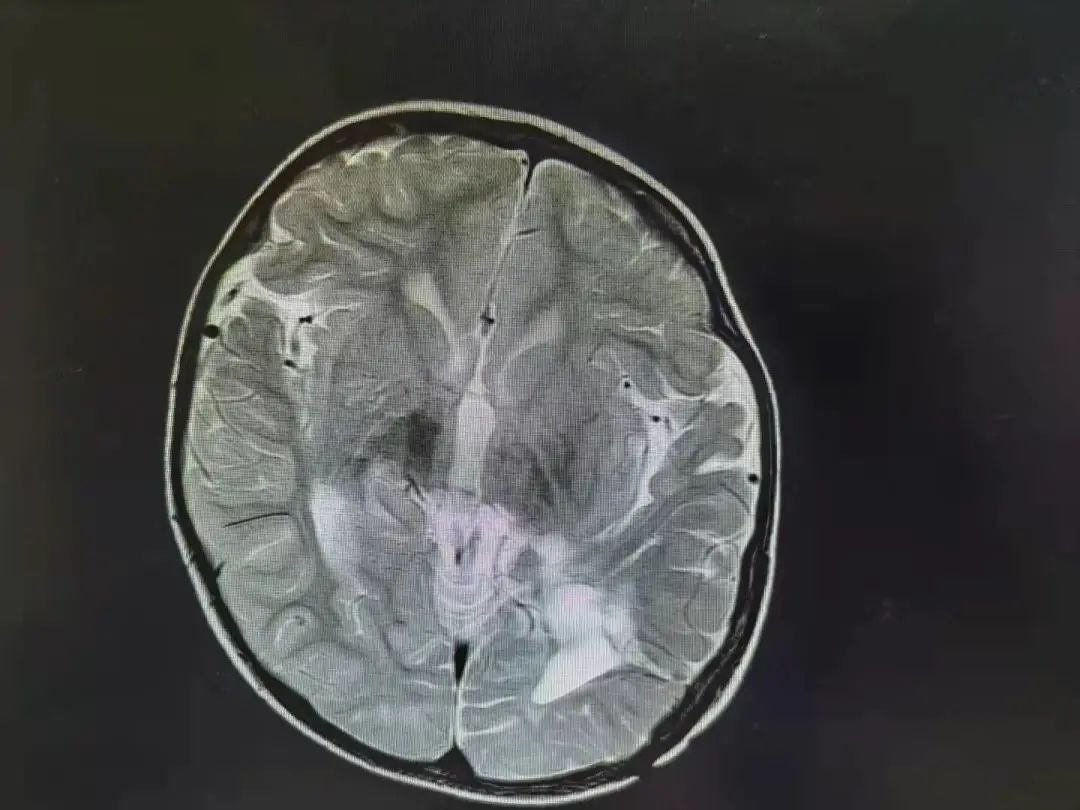

六六手术前脑部影像图

六六手术后脑部影响图 肿瘤已经消